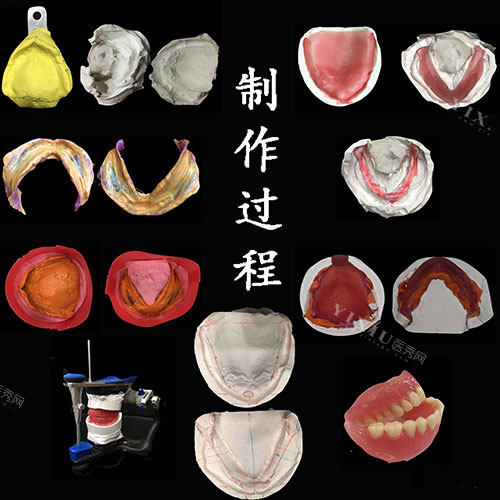

在技术方面,米兰口腔在牙齿修复领域积累了丰富经验。诊所采用较为成熟的操作方式,能够为不同需求的患者提供个性化方案。虽然价格相对较高,但整体体验值得这个价位。